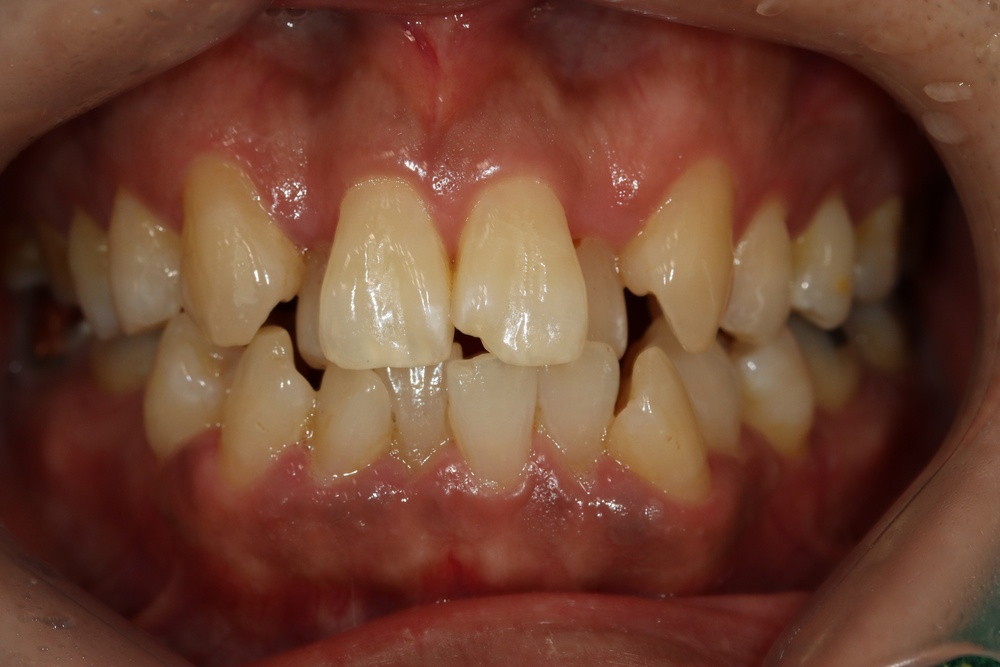

앞니가 비뚤게 나서 교정하러 온 친구입니다.

입천장의 고정식 확장장치를 이용해 좌우로 벌려서 치아를 배열할 공간을 만들었습니다.

그런데 친구가 학교에서 부딪혀서 다쳐 왔습니다.

바로 처치(치아를 철사로 부목 고정)후 신경치료를 진행하였습니다.

이후 치아배열을 마무리하여 가지런한 이를 가지게 되었습니다.